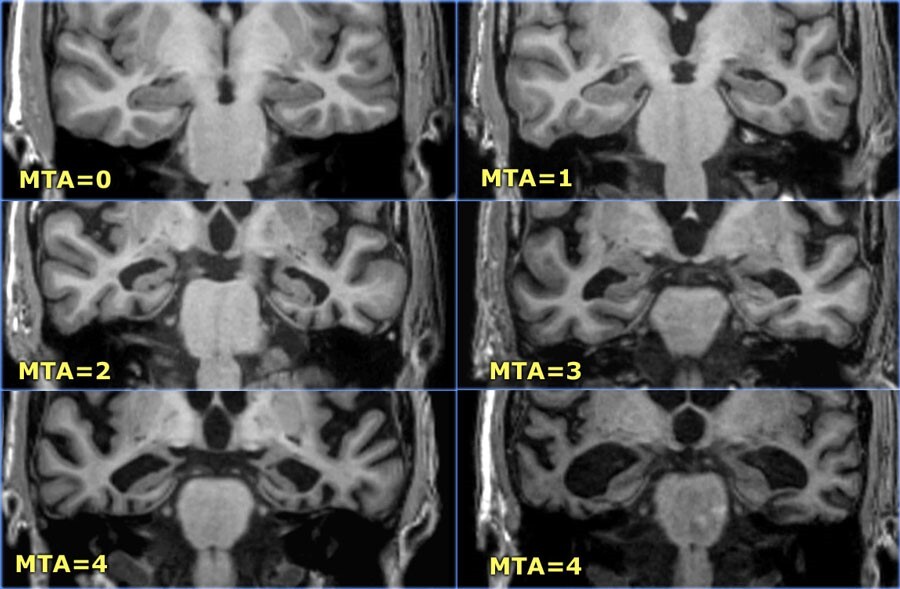

1) MTA-score (Шкала атрофии медиальных отделов височной доли)

Используемая для дифференциации умеренных когнитивных нарушений, изменений при болезни Альцгеймера от пациентов без нарушений.

Основывается на визуалиной оценке ширины хориоидальной щели, ширины височного рога и высоты гиппокампа:

0: нет атрофии

1: хориоидальная щель слегка дилатирована;

2: умеренная дилатация хориоидальной щели, слегка увеличенный височный рог бокового желудочка и слегка уменьшенный по высоте гиппокамп;

3: значительная дилатация хориоидальной щели, умеренное увеличение височного рога бокового желудочка и умеренное уменьшение высоты гиппокампа;

4: значительная дилатация хориоидальной щели, значительное увеличение височного рога бокового желудочка и значительная атрофия гиппокампа с потерей внутренней структуры.

< 75 лет: результат 2 или больше – патологические изменения.

> 75 лет: результат 3 или больше – патологические изменения.